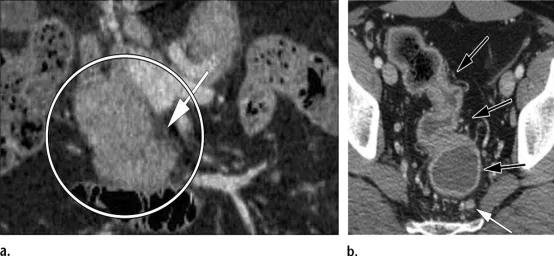

40岁男性,2型自身免疫性胰腺炎(AIP)。

(a图)冠状位增强CT示胰头区局灶肿物(白色圆圈),注意观察其轮廓光滑,正常胰腺小叶消失,以及低密度的纤维边缘(白色长箭头)。

(b图)CT图示乙状结肠黏膜增厚伴高强化。同时可见结肠周围血管充血(黑色长箭头)及淋巴结肿大(白色长箭头),结肠镜及活检符合溃疡性结肠炎。

42岁男性,2型自身免疫性胰腺炎

(a图)轴位T2WI示胰腺近端边界不清的等信号肿块样病变(白色长箭头)

(b图)冠状位T2WI示胰管管径变窄,并横穿同一区域(白色长箭头),注意观察胆总管远端的局灶性狭窄(白色短箭头)

(c图)轴位增强延迟期磁共振示同一区域的局灶性肿物样病变(白色短箭头),其余胰腺未见明确异常。

35岁女性,1型自身免疫性胰腺炎,(a图)轴位T2WI示低信号纤维化边缘(白色长箭头),(b图)轴位增强磁共振示均匀强化的胰腺以及不强化的纤维边缘(白色长箭头)。